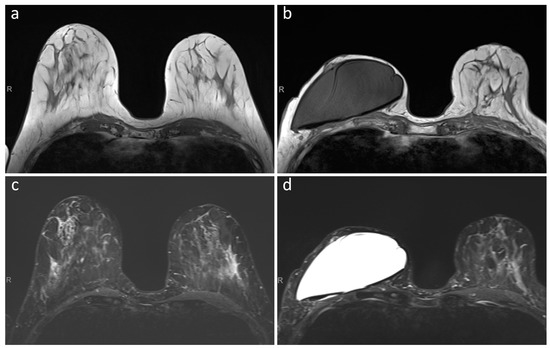

- Maximum diameter of the artifact caused by the RFID port on axial T1-weighted images (on the side with largest artifact in patients with bilateral expanders) and maximum diameter of the expander on the same axial plane, with calculation of their ratio.

- Maximum diameter of the RFID-related artifact.